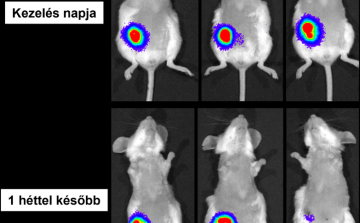

Új szárazságtűrő búzavonalat fejlesztettek a HUN-REN Agrártudományi Kutatóközpont Mezőgazdasági Intézet kutatói